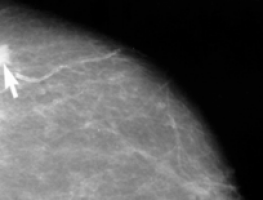

Women who develop breast cancer characterised as HER2-positive – approximately 1 in 5 of all breast cancers – are often treated with a drug called trastuzumab, commonly known by its brand name Herceptin, alongside standard chemotherapy drugs.